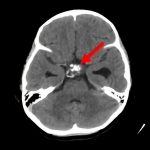

断層撮影

手術前1

手術前2